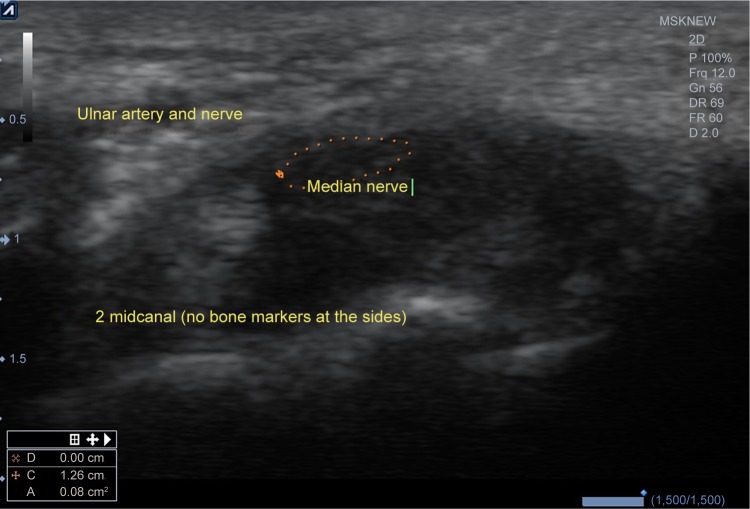

Midcanal area (eg, midway level between inlet and outlet) (Figure 2).

Figure 2.

Midcanal area (eg, midway level between inlet and outlet).